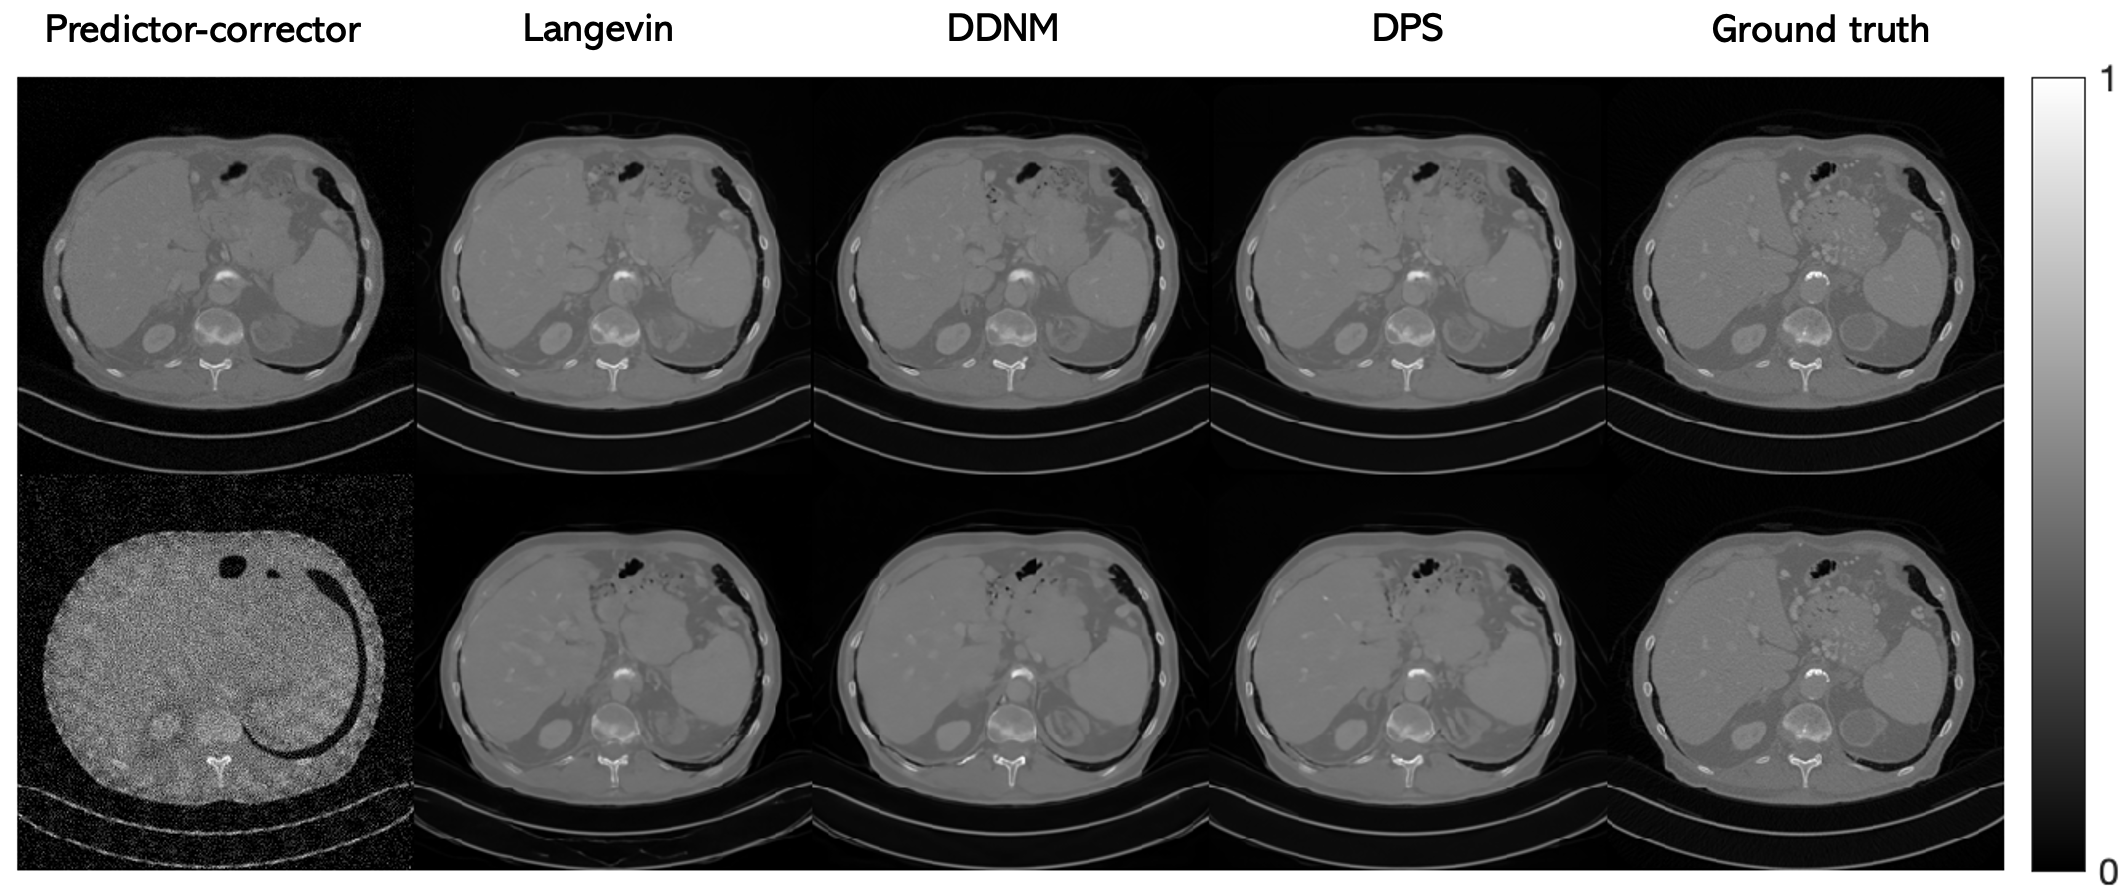

For further comparison of diffusion model methods, we implemented different sampling and data consistency algorithms and applied them in conjunction with our patch-based prior. In particular, we compared with Langevin dynamics [1], predictor-corrector sampling [19], and variation exploding DDNM (VE-DDNM) [7]. For all these sampling methods, we used the variation exploding framework for consistency and to avoid retraining the network. We also compared with two other ways of assembling priors of patches to form the prior of an entire image: patch averaging [23] and patch stitching [66]. App. A.5 contains pseudocode for these comparison algorithms.

Sampling methods.

One benefit of our proposed method is it provides a black box image prior for the entire image that can be computed purely through neural network operations on image patches. We demonstrate the versatility of this method by pairing a variety of different sampling and inverse problem solving algorithms with our patch-based image prior, along with comparisons with a whole-image prior. The implemented sampling methods include Langevin dynamics [1] with a gradient descent term for enforcing data fidelity step and the predictor-corrector method for solving SDEs  [19]. Since we observed better stability and results with Langevin dynamics, we also combined this sampling method with nullspace methods that rely on hard constraints  [7] and DPS [5]. To use the same neural network checkpoint across these implementations, we used the variance exploding SDE [2] method as the backbone for both training and reconstruction. DPS [5] and DDNM [7] were originally implemented with networks trained under the VP-SDE framework; here, we implemented those methods with the VE-SDE framework. Table 7 shows that generally, VE-DPS performed the best and that the patch-based method consistently outperformed the whole image method. However, the patch-based method still obtained reasonable results for all the implemented methods, showing that the learned image prior is indeed flexible enough to be paired with a variety of sampling algorithms. App. A.4 provides more details about the implemented algorithms.

Figure A.8 shows the results of using our proposed method compared with the whole-image diffusion model with different sampling and inverse problem solving algorithms. The predictor-corrector algorithm fails completely when using the whole-image model, indicating that this model could not be well-trained in this limited data setting. Quantitatively, DPS performs the best for PaDIS; visually, all of the methods obtain reasonable results, although some more minor artifacts are present in the first four methods. Nevertheless, this shows that the patch-based prior is flexible and can be used with a variety of existing algorithms.

Refer to caption

Figure A.8: Results of PaDIS for 20 view CT reconstruction using different sampling and inverse problem solving algorithms. Top row is with PaDIS and bottom row is with the whole-image model.